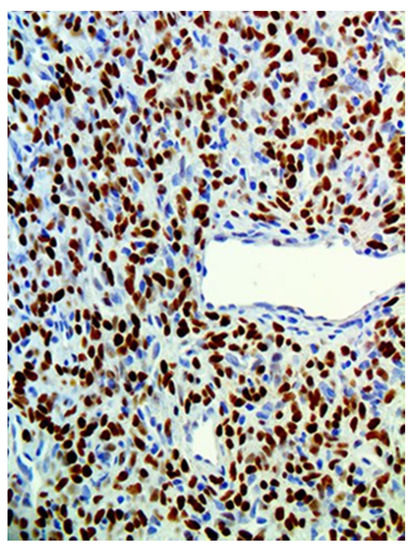

| Patients | CD34 | CD99 | STAT6 | Bcl-2 |

|---|---|---|---|---|

| 1 | + | + | + | NA |

| 2 | + | NA | + | NA |

| 3 | + | NA | + | + |

| 4 | + | NA | + | + |

| 5 | + | NA | + | NA |

| 6 | + | NA | + | + |

| 7 | + | NA | + | NA |